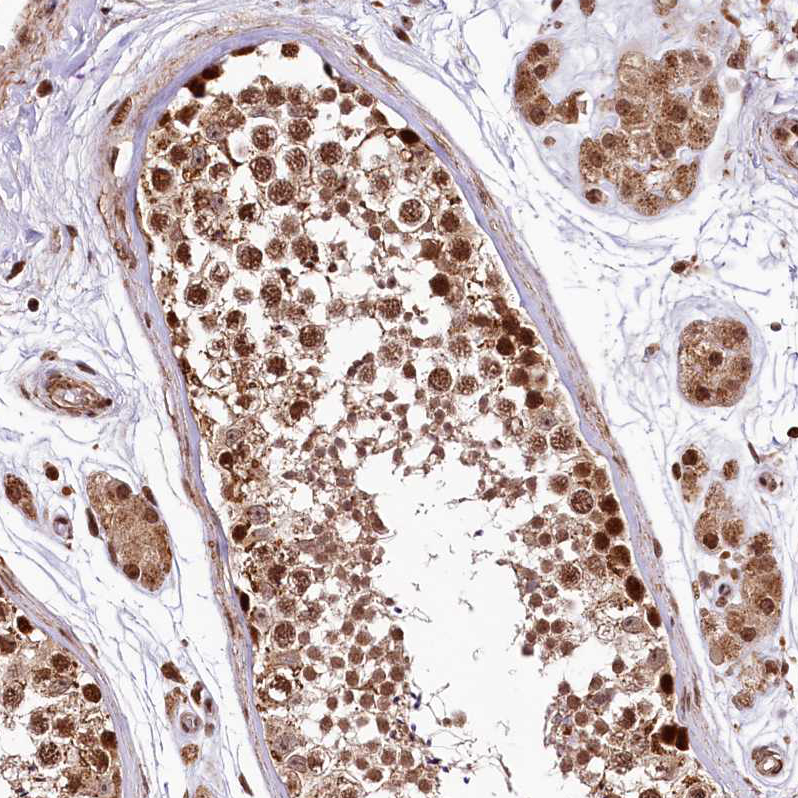

Immunohistochemical staining of human Testis shows strong nuclear positivity in cells in seminiferous ducts and Leydig cells.